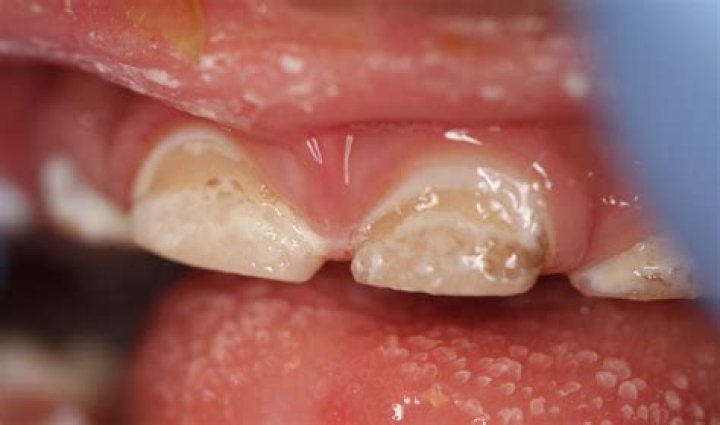

Plaque/Tartar Buildup Causing Tooth Stains

If your child's teeth are not being brushed at least 2 times per day for 2 minutes, bacteria may continue to collect and form plaque and tartar (hardened, calcified plaque). Plaque can be stained by beverages and foods, and tartar has a yellowish-brown color.

What is brown stuff on teeth?

When plaque builds up on teeth, it hardens into a substance called tartar, which is often a yellow or brown color. Tartar often appears along the gumline and in between your teeth, and regular brushing with toothpaste doesn't remove it.